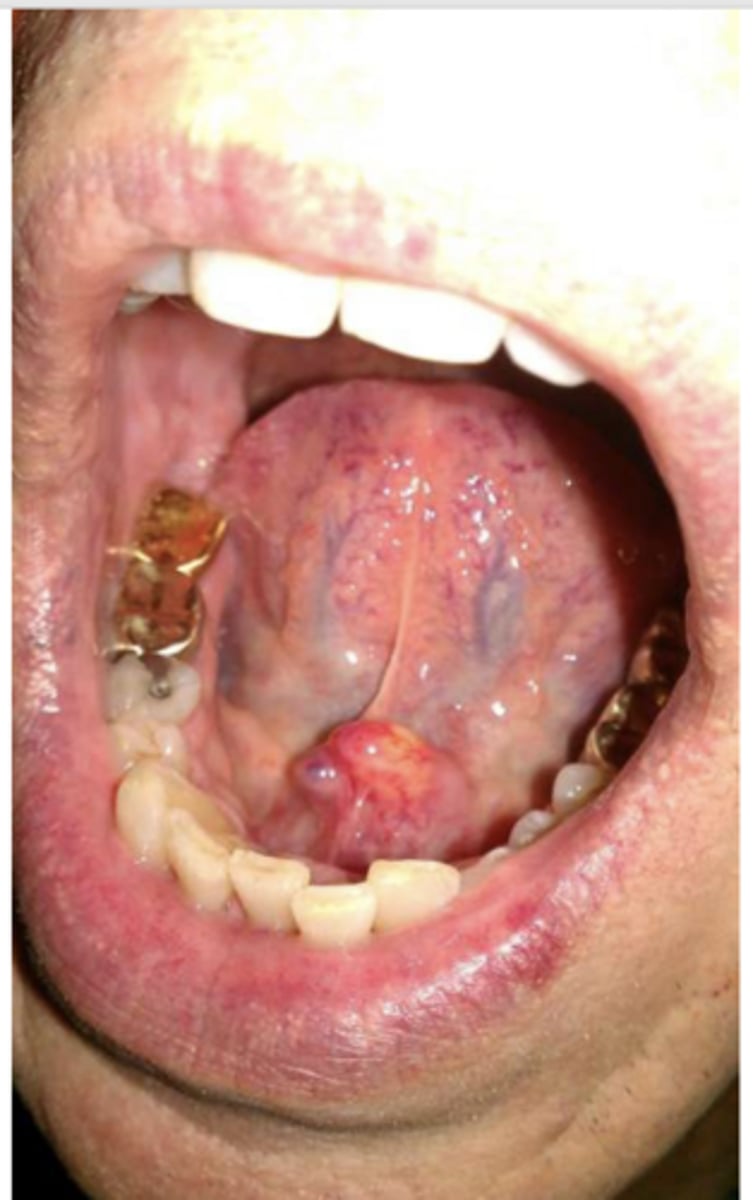

Necrotizing Sialometaplasia

Patient presents with single ulceration on the hard palatal mucosa. Patient claims it "used to be red and swollen, now it's like a crater". Histo path report reveals Acinar necrosis with preservation of lobular architecture, squamous metaplasia and Pseudoepitheliomatous hyperplasia. What is the diagnosis?

ID the pathology:

- Rare inflammatory, destructive condition of salivary glands

- Mimics malignancy clinically AND microscopically

- - Early swelling and erythema

- - Later ulceration

- Related to ischemia?

- Male predilection

- Initial swelling, then crater-like ulcer develops

- Rare destruction of palatal bone

hard palatal mucosa (75%)

The most common location for Necrotizing Sialometaplasia to present is the ______

ID the pathology based on the histology findings:

- Acinar necrosis with preservation of lobular architecture

- Squamous metaplasia

- Pseudoepitheliomatous hyperplasia

- Biopsy necessary to confirm diagnosis

- Resolves without treatment in 5-6 weeks

What is the treatment for Necrotizing Sialometaplasia?